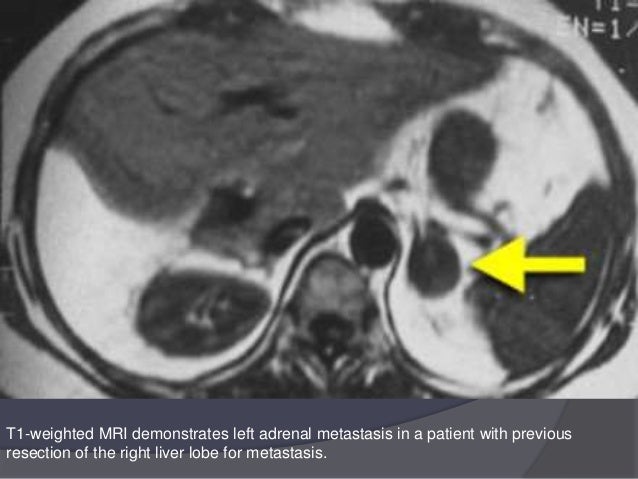

Solid Renal and Juxtarenal Lesions - Urinary Tract